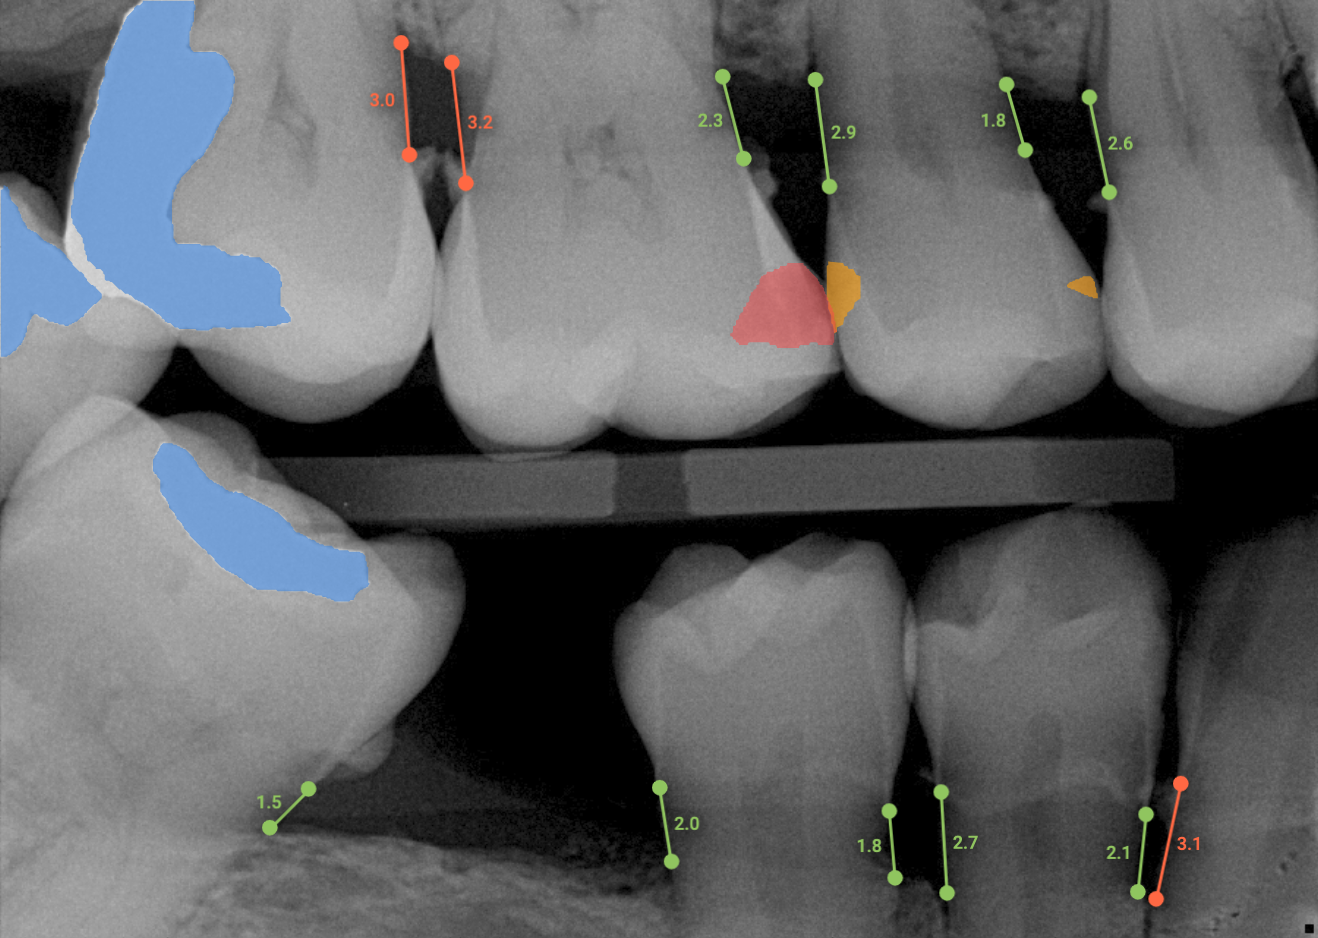

Overjet’s artificial intelligence technology transforms traditional black-and-white X-rays by adding a layer of data that instantly outlines decay (cavities) and measures bone loss. This makes it easy for you to see your results alongside your dentist.  It’s like getting a second opinion delivered instantly. With Overjet’s analysis and easy-to-read presentation, you will have the information you need to make an informed decision about your oral health. Together, we’ll review your findings and discuss the best steps to take to achieve your goals.

Overjet’s artificial intelligence technology transforms traditional black-and-white X-rays by adding a layer of data that instantly outlines decay (cavities) and measures bone loss. This makes it easy for you to see your results alongside your dentist.